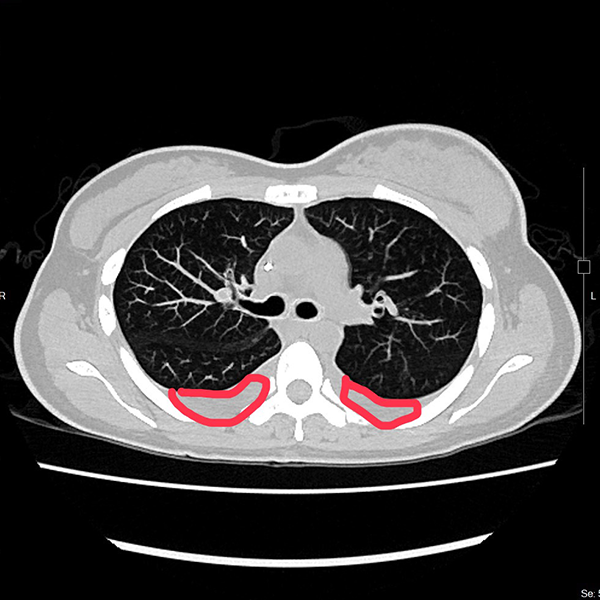

光田綜合醫院乳房外科廖志斌醫師指出,林小姐罹患的是最常見的「管腔型乳癌」,因此,醫療團隊評估屬於內臟轉移急症,先給於化學治療,之後再採用口服標靶合併荷爾蒙藥物治療。經過一段時間,林小姐的症狀逐漸獲得控制,生活品質明顯改善。

不過在2025年3月,癌症再次復發,甚至已經出現腹積水。且醫療團隊進一步檢查後發現,林小姐的癌細胞特徵有所變化,從原本的HER2陰性轉為HER2低表現(由0 分變為 2+,代表介於陰性與陽性之間),使其需接受新一代標靶治療。廖志斌醫師表示,這顯示乳癌是一種會隨著時間與治療而改變的疾病,並非一成不變,患者若出現復發或轉移,應再次接受檢測,以便調整治療方向。

目前林小姐已完成四次新型標靶合併荷爾蒙治療,不僅原有的呼吸困難症狀大幅改善,也能恢復正常日常活動。她分享心情說:「還好有醫師幫忙,我現在過得比想像中更好。」她也提醒其他患者,與其擔心病情,不如保持正向心態,積極面對治療。